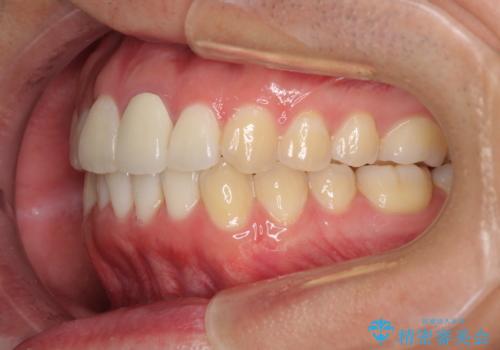

前歯の歯並びとクラウンを改善 インビザラインとオールセラミック

- 前歯の歯並びと不自然な色をした前歯のクラウンを気にして来院された患者様です。

上下前歯の歯列不正はインビザラインにより歯列を整え、その後に、前歯をオーダーメイドタイプのオールセラミッククラウンにて補綴治療することとしました。

初診時には、歯並びを整えることのみを検討されていましたが、歯列が整うにつれて不自然な色合いが気になるようになり、矯正治療を行ってから補綴治療をする計画を受け入れてくださいました。

口元の印象が明るく変わり、患者様には大変満足していただきました。